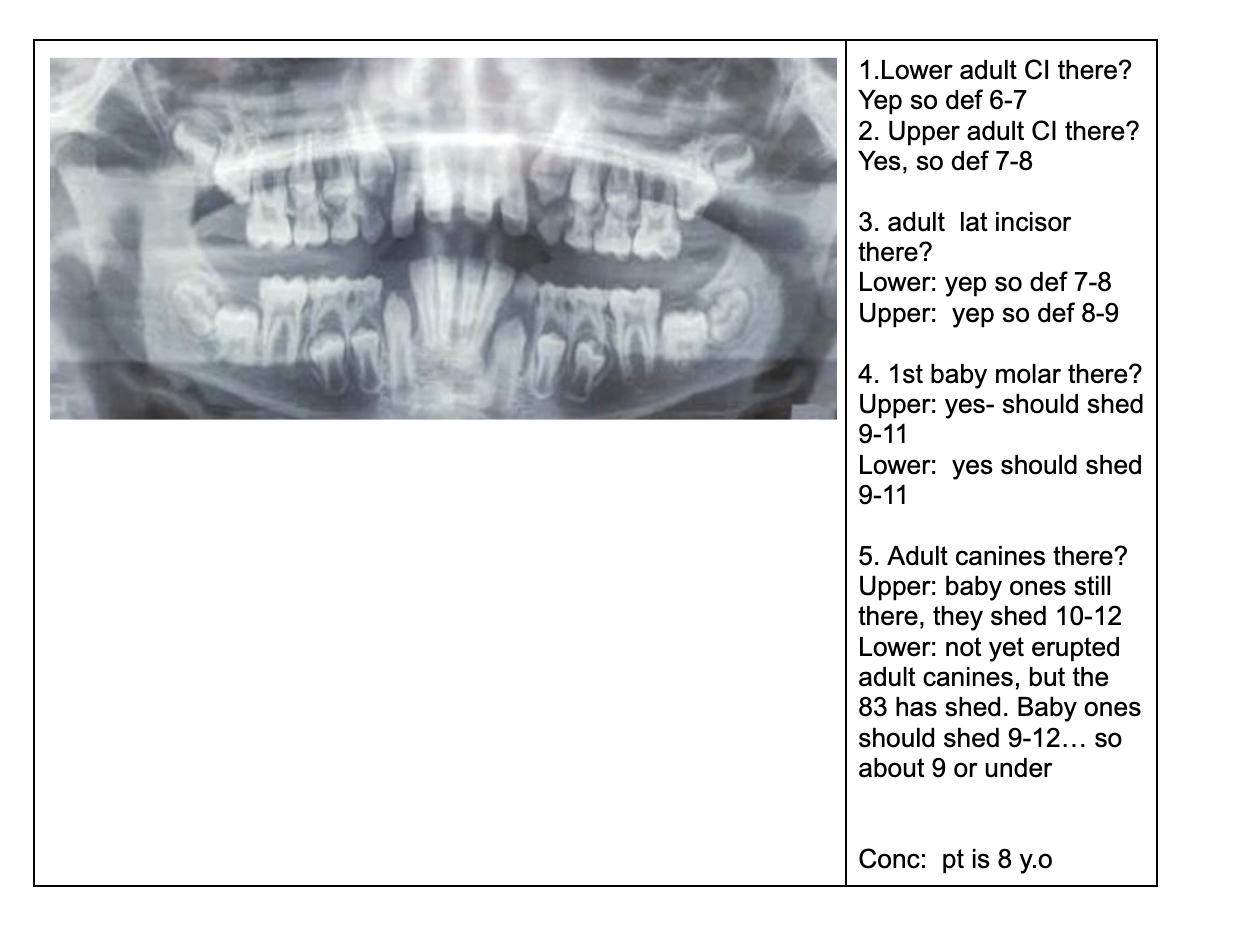

1.lower adult CI there? YES, so def 6-7

1. Upper Ad. Ci there? NO, so either 6-7 or under

Last molar crown not really formed so 6?

NOTE- THE 8’s - crown starts developing at 9 yo.